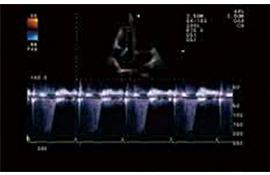

TDI組織多普勒成像

TDI已成為重要的心臟功能評估技術(shù),能夠精確分析高幅、低頻多譜勒頻移及通過彩色編碼實時顯示心肌組織的運動速度。TDI能夠無創(chuàng)診斷心肌收縮、舒張的速度,進行左室收縮、舒張功能的評價,特別在舒張功能的評價方面,TDI能夠在收縮功能受累之前的心肌運動低下的病人得到早期的診斷,并得出沿室壁內(nèi)膜運動的速度,用以評價左室節(jié)段運動的狀態(tài),獲得高質(zhì)量的多譜勒信息,測出速度、平均速度和瞬間加速度等參數(shù)值。此項技術(shù)為臨床冠心病、心肌病、心律失常等多種疾病的診斷提供了可靠的診斷依據(jù)。